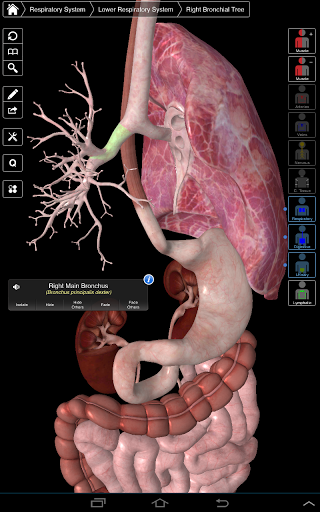

Essential Anatomy 3 représente la toute dernière technologie 3D révolutionnaire et un design innovant. Un moteur graphique 3D de pointe, construit sur mesure par 3D4Medical à partir de zéro, alimente un modèle anatomique très détaillé et fournit des graphiques de qualité exceptionnelle qu'aucun autre concurrent ne peut atteindre.

L'application représente une approche unique à l'apprentissage de l'anatomie générale. Les graphismes sont inégalés et rendent l'apprentissage, grâce à l'utilisation de contenu informatif et de fonctionnalités innovantes, une expérience riche et engageante.

⁃Respiratoire

NOUVELLE TECHNOLOGIE 3D

Essential Anatomy 3 est réactif, visuellement magnifique et sans effort. L'application est entièrement 3D, ce qui signifie que vous pouvez voir n'importe quelle structure anatomique dans l'isolement, ainsi que de n'importe quel angle.